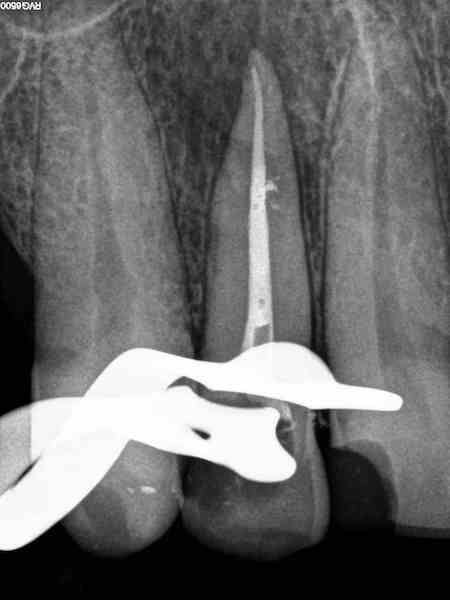

De endodontie of wortelkanaalbehandeling bestaat uit het verwijderen van zenuwen die zich in de wortels van de tanden bevinden. Na het verwijderen zal de tand weer opgevuld worden. Deze behandeling zal u weer een comfortabel gevoel geven.